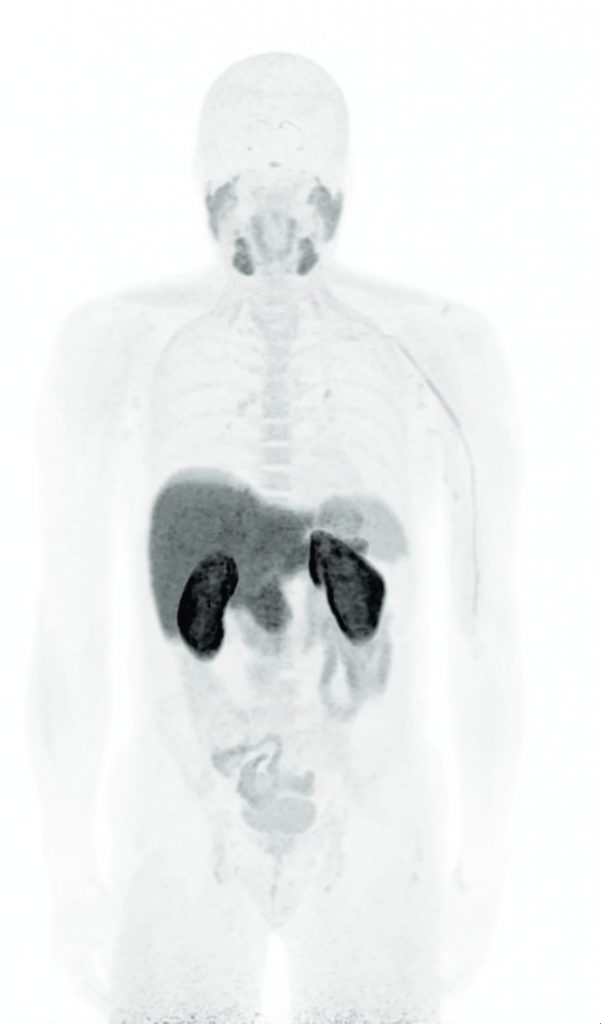

Fig. 132.7 TEP à la fluorocholine (18FCH).

Image MIP mettant en évidence la distribution physiologique du traceur.